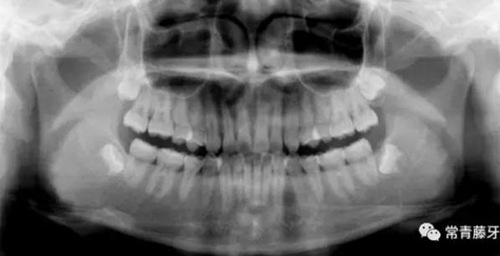

影像學(xué)檢查

全口曲斷顯示A1B1根尖存在吸收。

頭影測量顯示為骨性Ⅱ類低角患者。